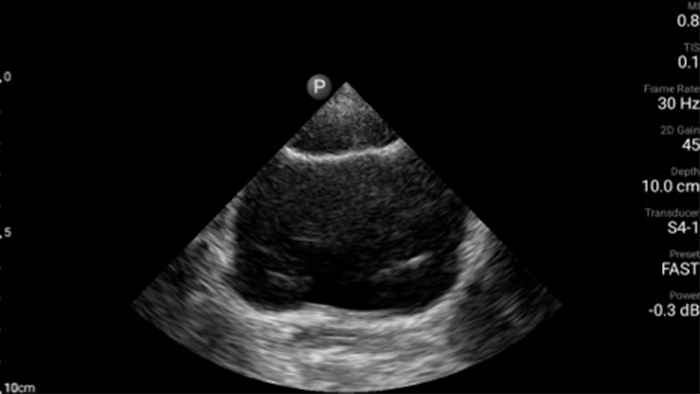

Early detection can help keep conditions from becoming critical

Congestive heart failure is a growing issue today. Discovering it earlier with in-office ultrasound can greatly improve survival rates.

Case study

Cardiac tamponade masquerades as abdominal pain

Assessment of left ventricular function